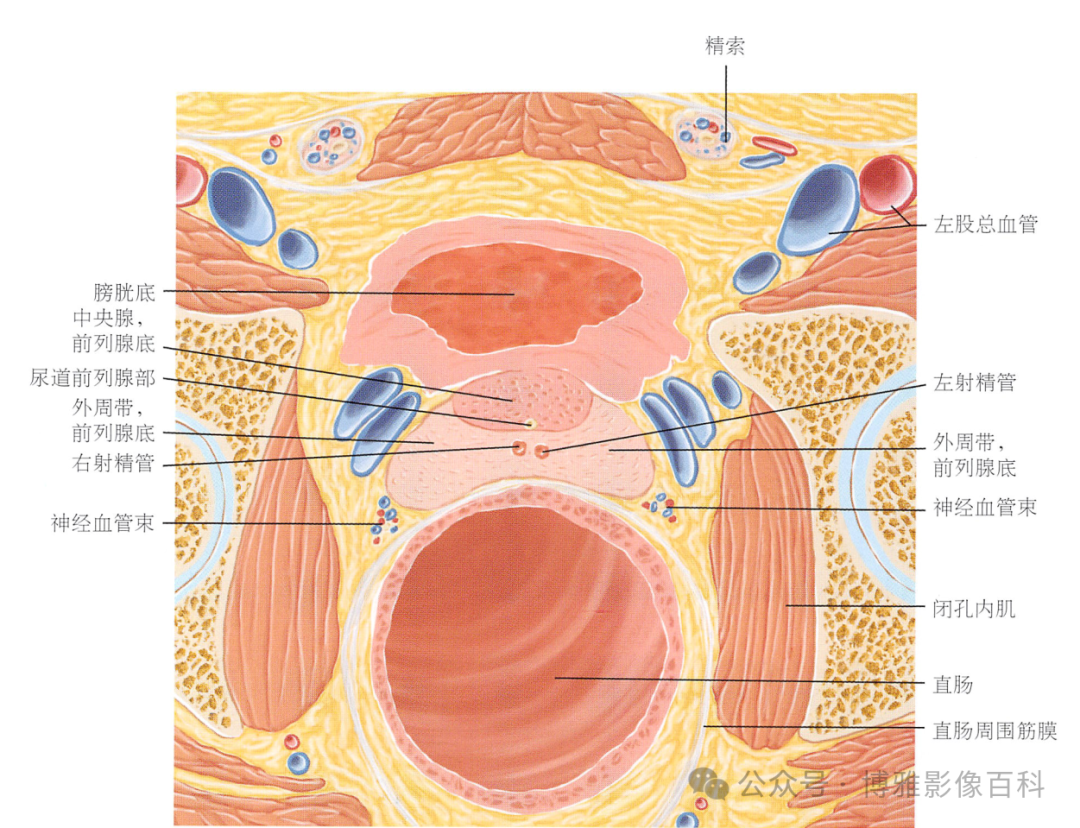

70-75% 的前列腺癌起源于外周带 (PZ)。该区域的后部可以通过直肠指检进行检查。

25% 的前列腺癌起源于移行带 (TZ)。极少数前列腺癌出现在中央带或前纤维肌基质中。

MR 解剖学

前列腺良性增生患者的轴向T2 图像,其他方面正常。外周带是一薄层均匀的高信号,边界清晰连续性的低信号包膜。移行带通常表现为不均匀中等信号,病灶被边界清楚的BPH良性前列腺增生结节所取代。精囊具有均匀T2高信号。未见淋巴结肿大。